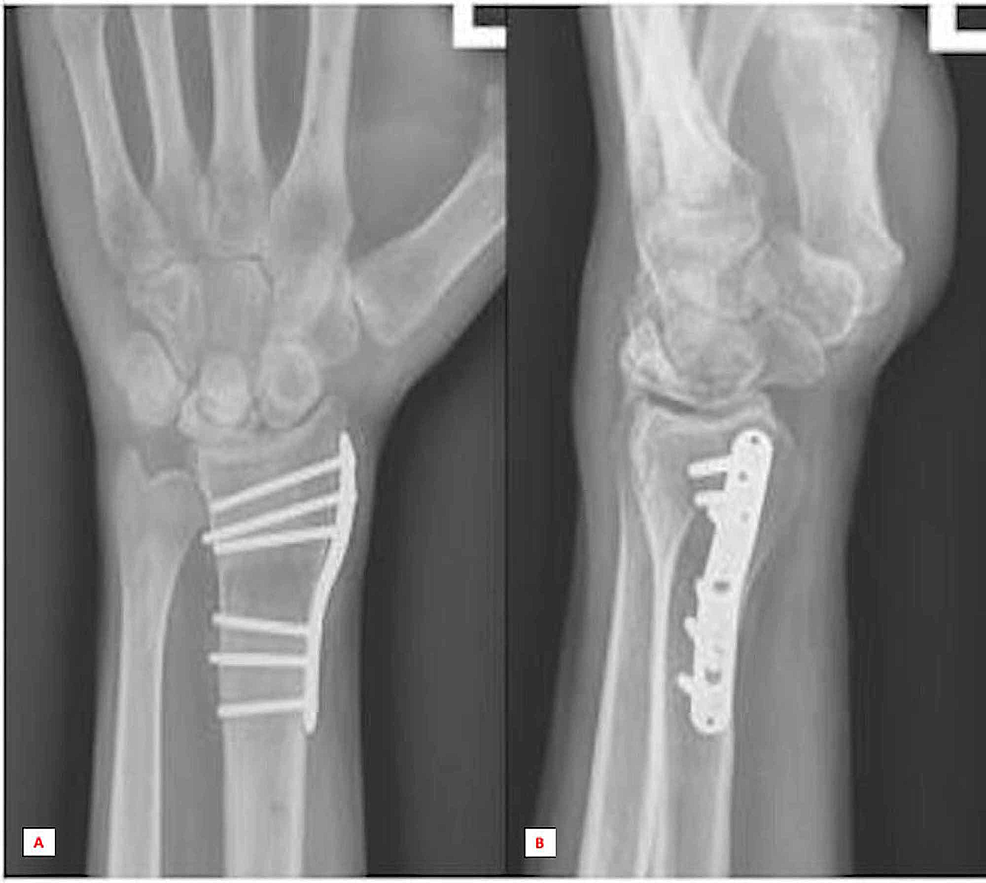

Avascular Necrosis of the Lunate Following Reconstruction of the

Avascular Necrosis of the Lunate Following Reconstruction of the What Is Avascular Necrosis Of The Lunate kienbock's disease (kd) is defined by avascular necrosis of lunate with a predictable pattern of lunate collapse, carpal change, and degeneration, resulting. kienböck disease refers to avascular necrosis of the lunate carpal bone, known as lunatomalacia. kienbock’s disease occurs when a wrist bone named the lunate loses its blood supply. kienbock's disease is the avascular necrosis. What Is Avascular Necrosis Of The Lunate.